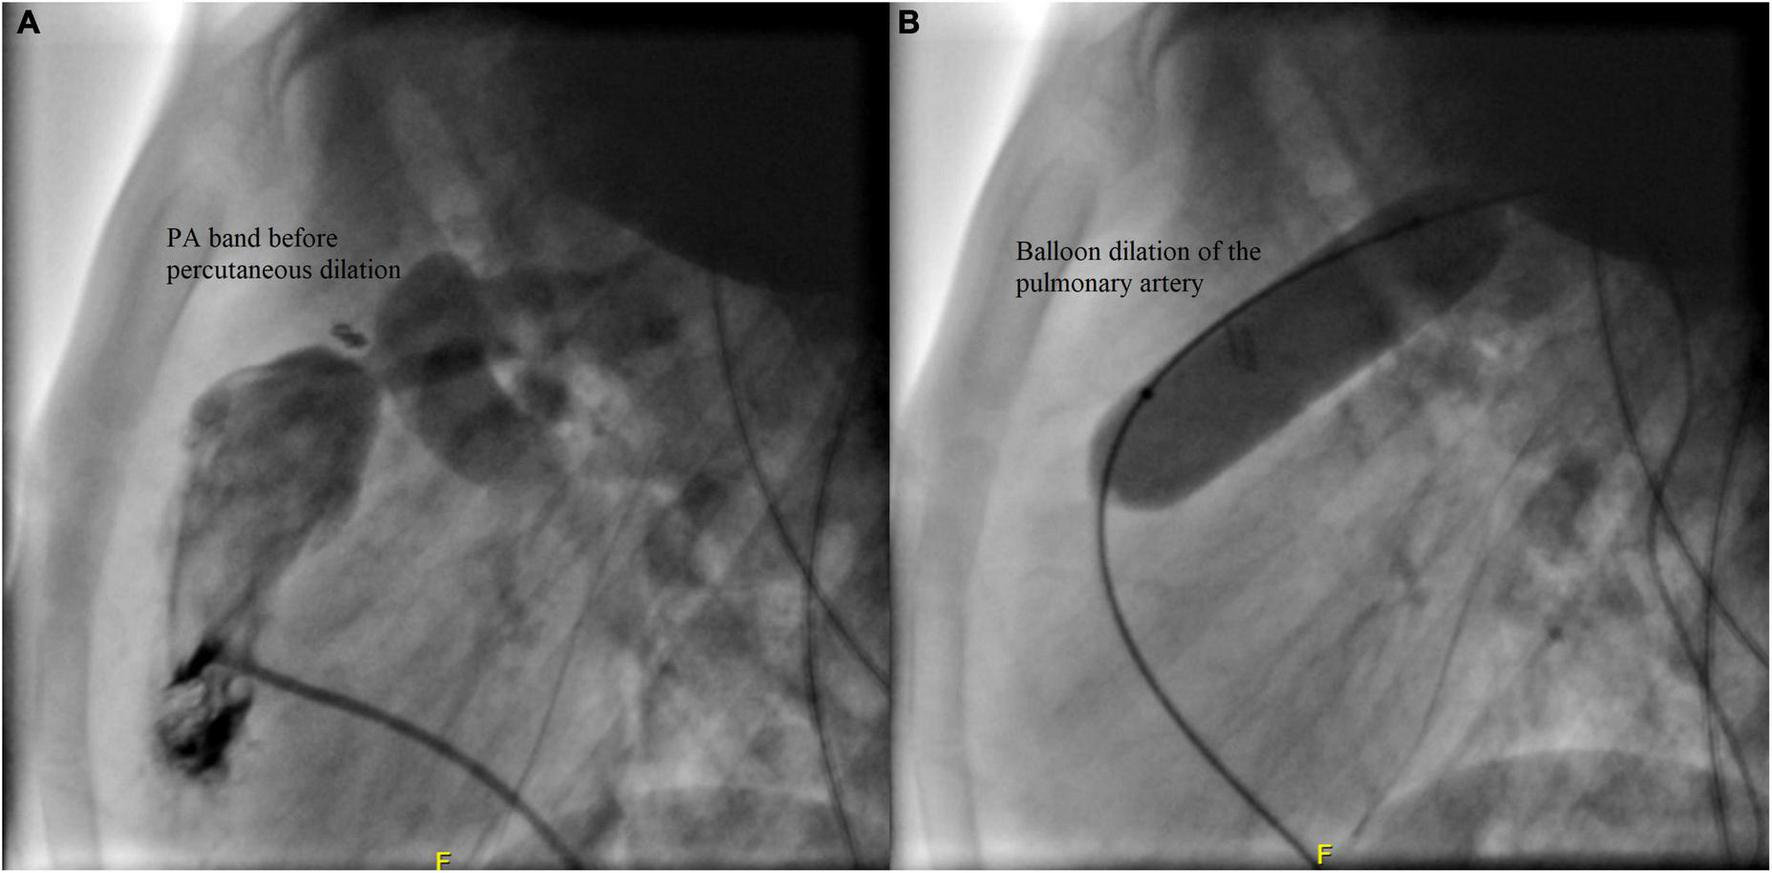

Case II: A male patient was diagnosed at the age of 2 months with multiple apical muscular VSDs that are moderate to large. He had successful PA band placement at 4 months of age due to pulmonary overflow. He presented at the age of 4 years for catheter-based removal of his PA band. Before the procedure, echocardiography revealed severe narrowing of the PA with a systolic gradient of 85 mmHg across the band, an RV systolic pressure of 105 mmHg, and a PA systolic pressure of 20 mmHg. Following sedation, successful balloon dilation of the PA band was performed using a 15 mm balloon, which resulted in a reduced RV pressure of 38 mmHg, a residual gradient of 8 mmHg across the PA band, and a PA systolic pressure of 30 mmHg. On the same day post-debanding, the patient was free of pain according to the FLACC scale. No complications were encountered during or after the procedure, and he didn’t require further intervention. The angiographic findings of the patient before and after the angioplasty are shown in Figure 5.

FIGURE 5

Angiographic findings of Case II before (A) and after (B) the debanding procedure.